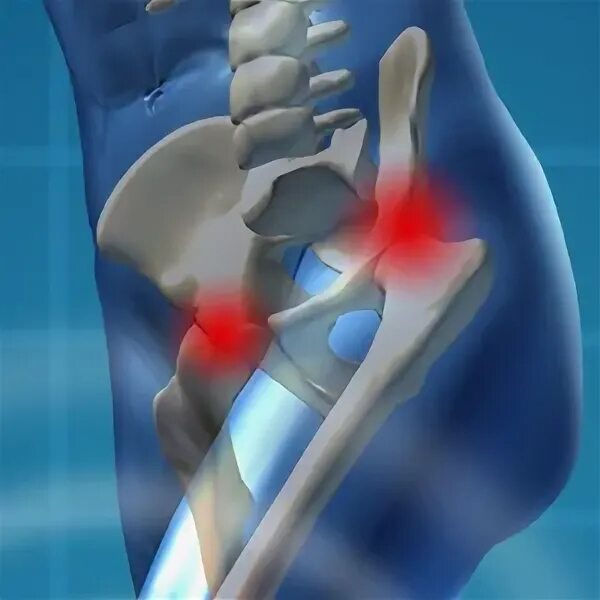

Инвалидность при некрозе тазобедренного сустава